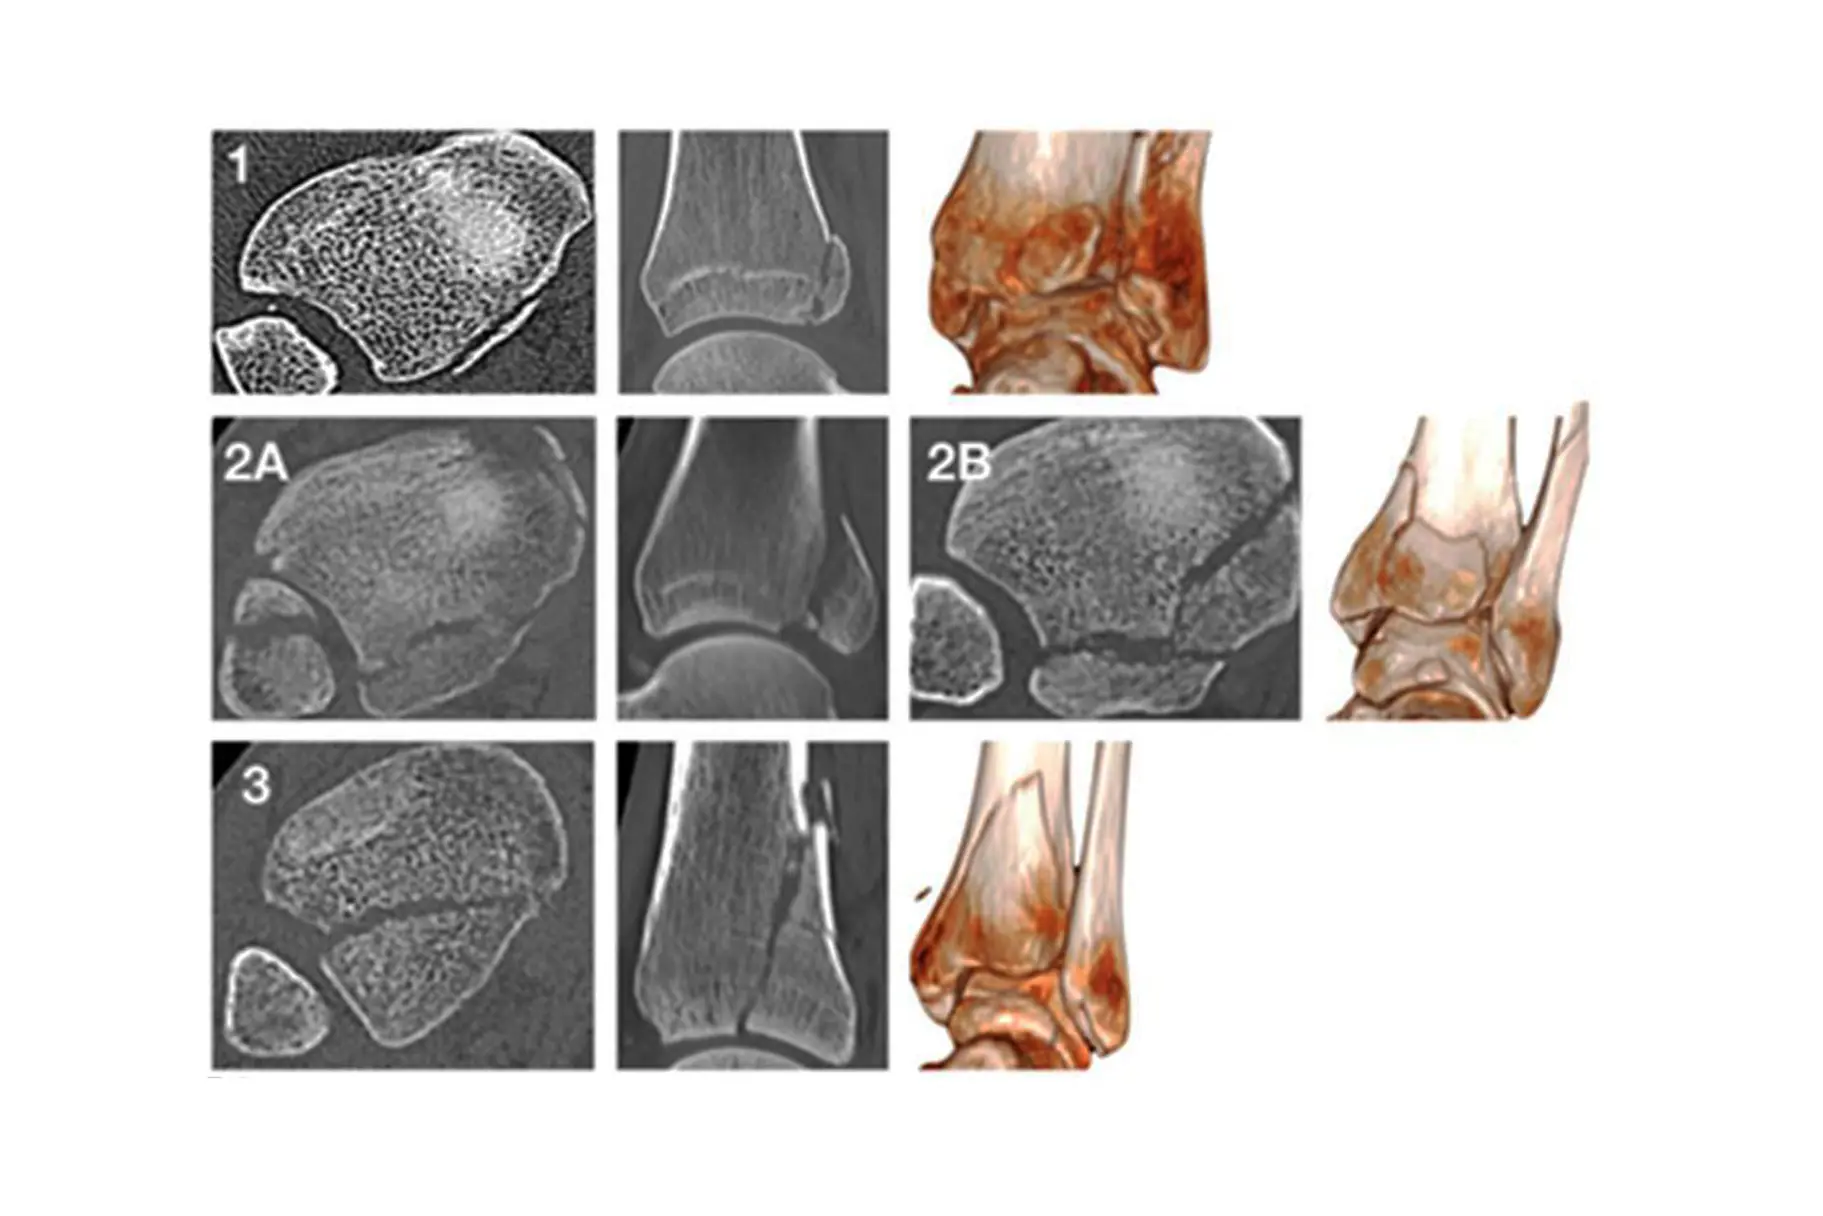

Illustrasjon: Mason LW, Kaye A, Widnall J, Redfern J, Molloy A. Posterior Malleolar Ankle Fractures: An Effort at Improving Outcomes. JB JS open access. 2019;4(2):e0058. doi:10.2106/JBJS.OA.18.00058

Type 1: Ekstraartikulær avulsjon, mindre skallfragmenter

Type 2A: Posterolateralt fragment som involverer fibular notch

Type 2B: Posterolateralt fragment som involverer fibular notch, og et postero-medialt fragment som ligger foran dette.

Type 3: Fragmentet involverer hele den bakre tibiaplafonden - Alder 18-65 år